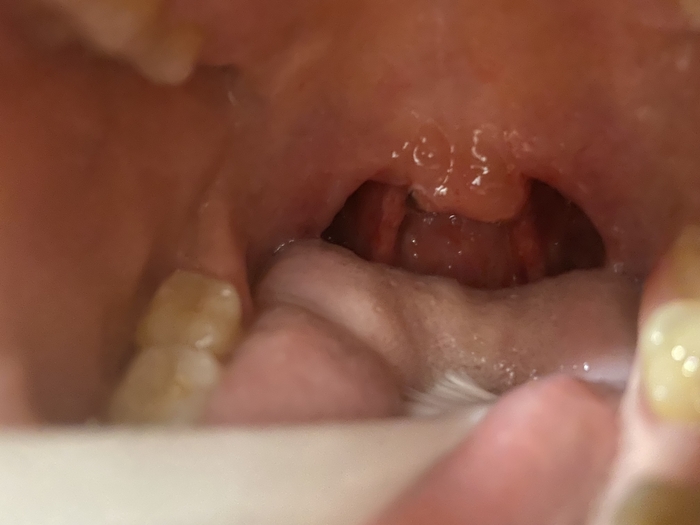

Гипертрофия миндалин и аденоидов у ребенка1

Доброго времени суток. Очень нужна консультация отоларинголога. Сегодня 02.02.23 была со своей дочкой в НМИЦ Отоларингологии в Москве на консультации. Дочке 3,5 года, ставят диагноз гипертрофия миндалин с гипертрофией аденоидов III степени. Показана эндоскопическая шейверная аденотомия, двусторонняя тонзиллотомия. Записали на операцию по ОМС на 03.07.23. Можно раньше, но платно. Сумму обозначили приличную для моей семьи.

Но меня очень беспокоит то, что ночью доча очень тяжело дышит уже даже ртом, имеют место быть эпизоды апноэ по 5-6 секунд несколько раз за час сна. Из-за этого сон беспокойный.